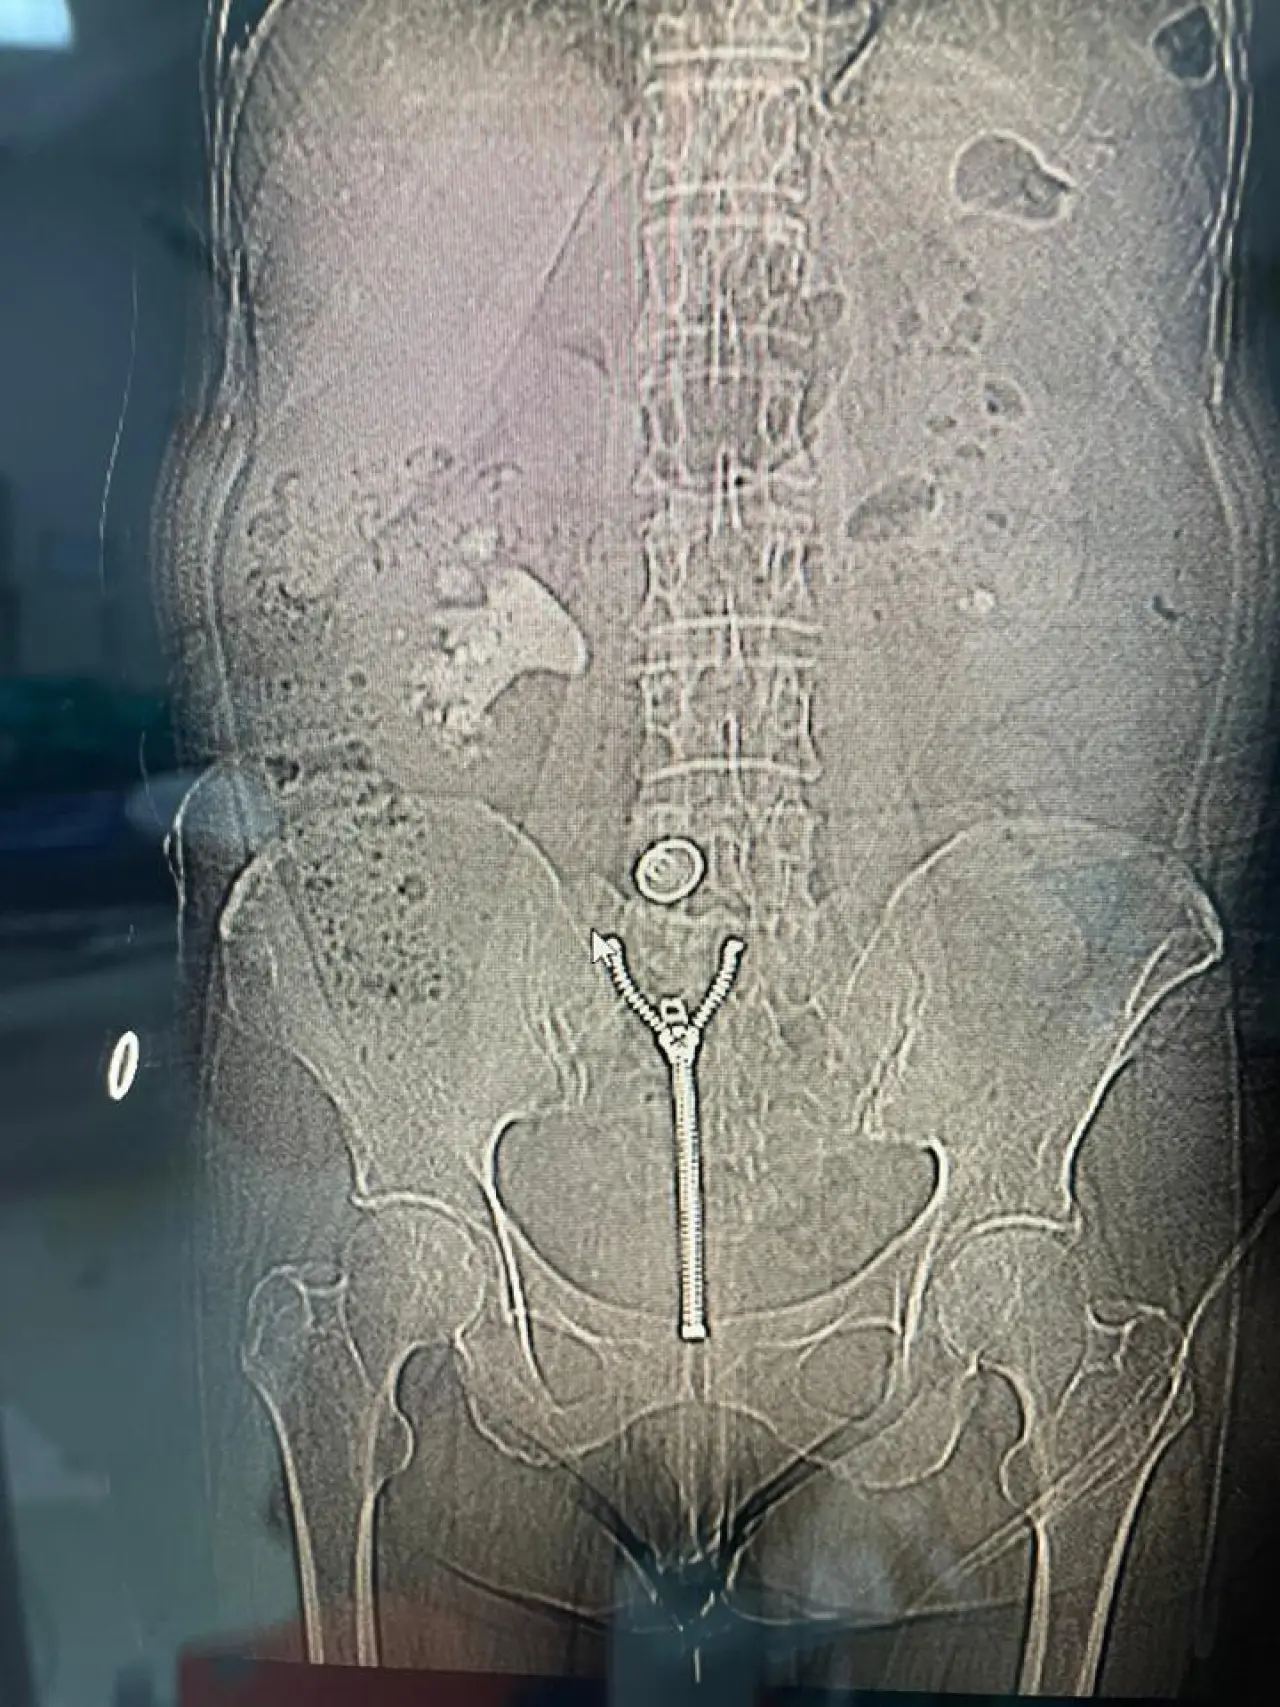

Malatya'da 58 yaşındaki bir hastanın böbreğindeki 8 santimetrelik taş kapalı ameliyatla başarıyla çıkarıldı.

Üroloji uzmanları tarafından yapılan ameliyatta, perkütan nefrolitotomi yöntemi tercih edildi. Bu teknik sayesinde böbrek fonksiyonları korundu ve hasta hızla iyileşti.

Operasyonu gerçekleştiren doktorlar, taşın büyüklüğüne dikkat çekerek kompleks bir süreç olduğunu belirtti. Kapalı yöntemin avantajlarıyla hasta kısa sürede sağlığına kavuştu.

Hasta, çıkan taşın neredeyse yarım su bardağı kadar olduğunu ifade etti. Ameliyat sonrası normal hayatına hızla döndüğünü ve memnuniyetini dile getirdi.